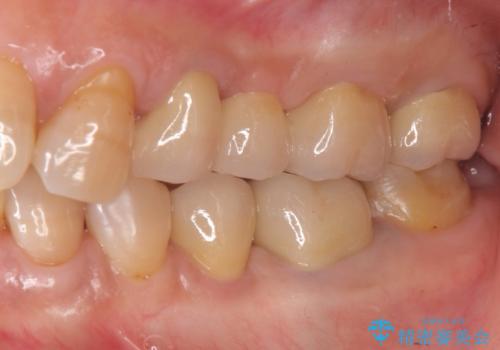

外から見てもなかなかわかりませんが、左側奥歯に大きな虫歯がX線写真で認められるので矯正治療前に虫歯治療を行っていきます。

今回矯正治療に先んじて行われたX 線写真検査により大きな虫歯が見つかり、先に処置を行うことができました。